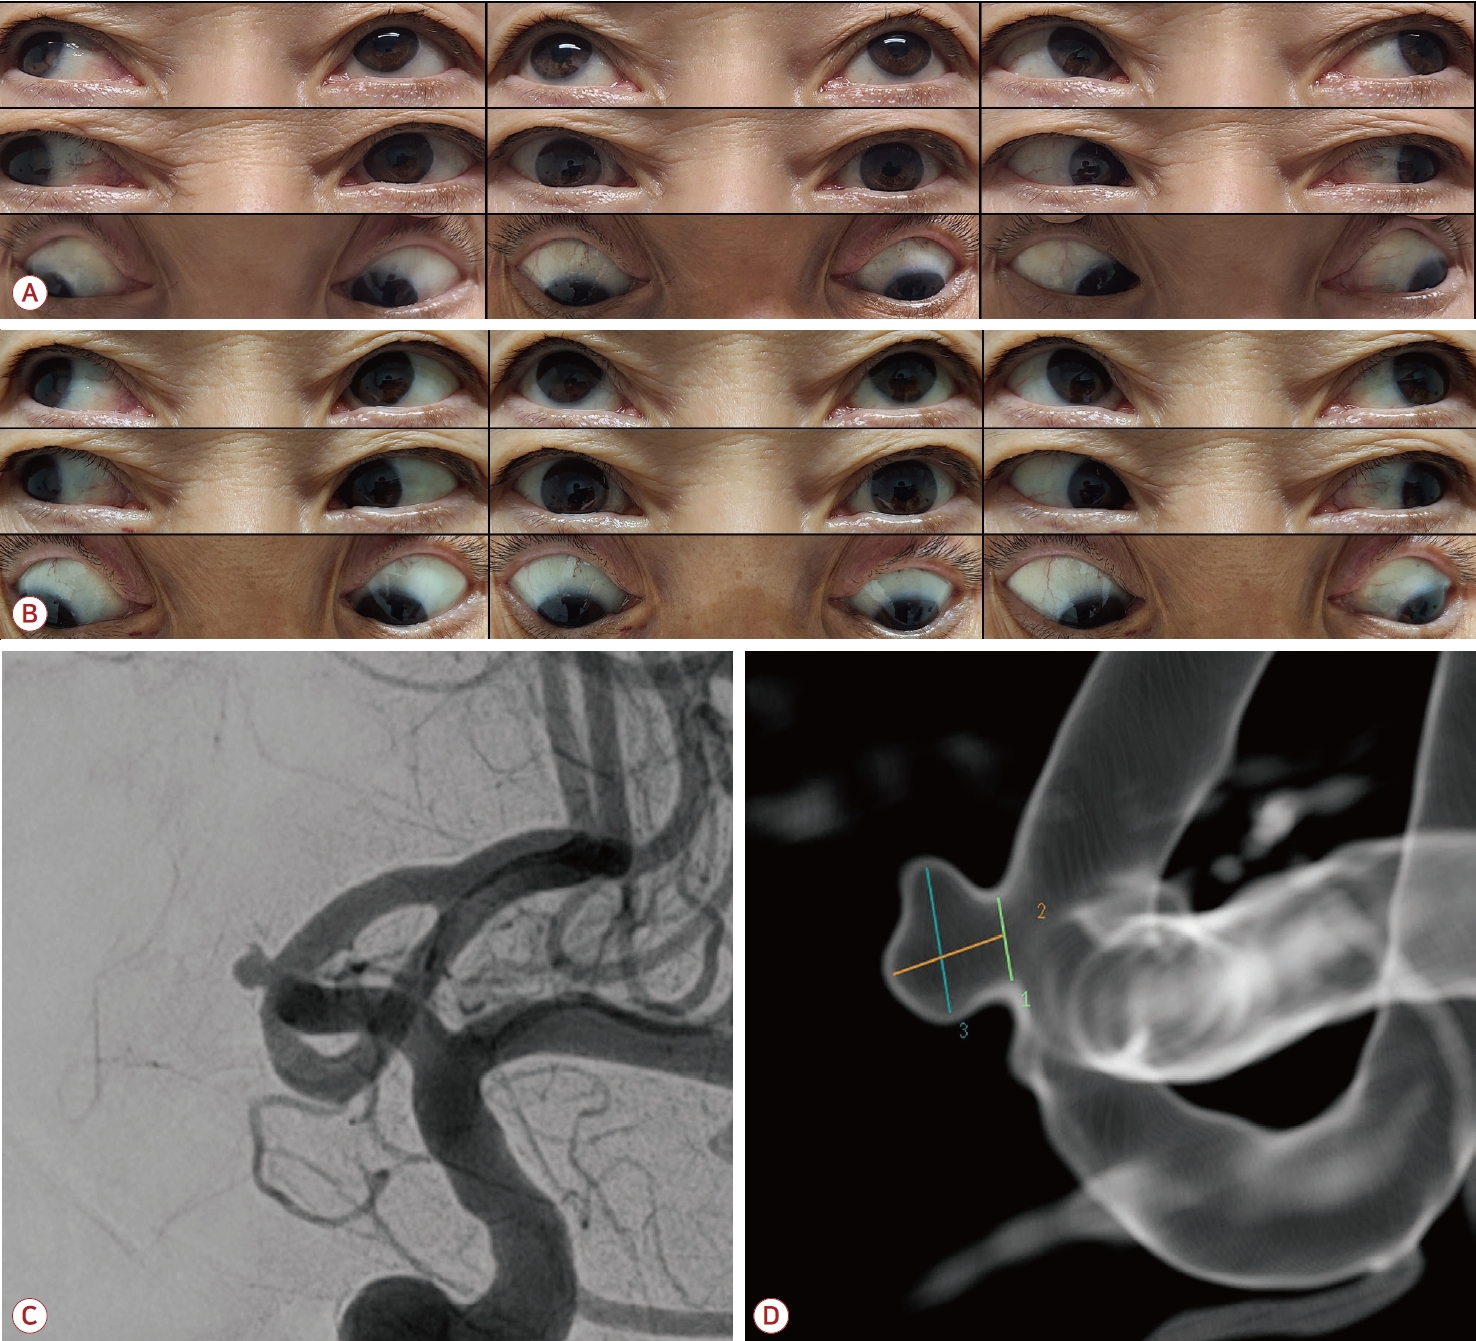

70세 여자가 4일 전부터 갑자기 시작된 두통 및 1일 전부터 시작된 수평복시로 응급실에 왔다. 머리 전반에 걸친 두통은 특히 왼쪽 안구 내측부터 후두부까지 당기는 듯한 양상이었고, 보행 시 물체가 2개로 보이며 어지럽다고 하였다. 신 체 진찰에서 혈압은 159/89 mmHg, 맥박수는 74회/분으로 확인되었으며 안구돌출이나 안구충혈, 안검하수, 안구편위 소견은 관찰되지 않았다. 신경계 진찰에서 좌안의 내전장애 및 우측 주시 시 유발되는 수평복시가 관찰되었다. 해리안진(dissociated nystagmus)이나 단속안구운동(saccade)의 이상 소견은 없었다. 동공 크기와 빛반사를 포함한 뇌신경검사, 사지의 운동, 감각검사 그리고 심부건반사에서도 모두 정상이었다. 환자는 고지혈증에 대해 치료 중이며 혈액검사에서 총 콜레스테롤 208 mg/dL (정상범위 <220 mg/dL), 저밀도 지질단백 137 mg/dL (정상범위 <140 mg/dL)가 상승되어 있었다. 당화혈색소, 갑상선호르몬검사, 요검사, 심전도, 가슴X선에서 다른 혈관 위험인자는 발견되지 않았다. 입원 당일 시행한 뇌자기공명영상에서 외안근, 경정맥동, 내경동맥에 이상 소견이 관찰되지 않았고 확산강조영상에서도 급성 허혈병변이 보이지 않았다. 전교통동맥에 작은 동맥류가 확인되었으나 증상과 무관할 것으로 판단하였고, 급성 허혈성 INO에 준하여 항혈소판제(아스피린 100 mg/일, 실로스타졸 100 mg/일) 및 고농도 스타틴(로수바스타틴 20 mg/일) 치료를 시작하였다. 입원 4일 차, 환자는 지속적인 두통, 수평복시 등을 호소하였고 뇌줄기의 허혈성 병변을 확인하기 위해 추가로 시행한 확산 강조영상 및 T2영상에서 급성 뇌경색을 시사하는 소견은 관찰되지 않았다. 보다 상세한 신경학적 진찰상 내전장애는 전정 안구반사(vestibulo-ocular reflex, VOR)에 의해 극복되지 않았고, 근접반사(near reflex)에서 눈모음(convergence)의 제한이 관찰되어 INO보다 눈돌림신경의 부분 마비에 의한 내측직근 단독 마비로 판단되었다(Fig. A). 대퇴동맥경유뇌혈관 조영술(transfemoral cerebral angiography)에서 전교통 동맥에 width×height×neck 2.22×1.83×1.27 mm의 작은 동맥류가 관찰되었으나 천장(dome)에서 최근 파열이 강하게 의심되는 모양의 딸낭(daughter sac 또는 bleb)이 관찰되었다(Fig. C, D). 입원 5일 차 전신마취하에 코일색전술을 시행하였다. 시술 직후부터 환자의 두통, 안구통은 소실되었고, 좌안 내측직근 마비의 완전한 회복을 보이며 입원 7일 차에 퇴원하였다(Fig. B).

Neuroimaging and eye findings of the patient. (A) The nine-gaze photograph shows partially limited adduction of the right eye (white arrowhead) without evidence of other combined oculomotor nerve palsy. (B) Follow up nine-gaze photograph shows the complete recovery of the adduction limit of the right eye 2 days after endovascular obliteration of the anterior communicating artery aneurysm. (white arrowhead). (C) DSA shows a tiny saccular aneurysm with a prominent daughter sac of the left ACoA which is a suspicious finding of the recent aneurysmal rupture. (D) DSA demonstrated a small blister aneurysm at the medial aspect of the left ACoA, with a size of 2.22×1.83×1.27 mm (width×height×neck). DSA; digital subtraction angiography, ACoA; anterior communicating artery.